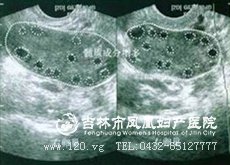

一、超声检查

双侧卵巢多囊性增大,被膜增厚回声强。被膜下可见数目较多,直径2~9mm囊状卵泡一侧或者两侧各有10各以上。围绕卵巢边缘,呈车轮状排列,称为项链征。卵巢间质回声不均,子宫内膜肥厚,应注意排除子宫和卵巢肿瘤及肾上腺病变。

B超是能够准确检查出多囊卵巢综合症的。

B超是多囊卵巢综合症的常规检查方法之一,其主要是通过直观的查看到体内的具体情况来判断是否患有多囊卵巢综合症。主要特点如下:

1、能够看见的小囊数目多,直径通常是在3至8mm左右的囊状卵泡。一般会在一侧出现10个,甚至有更多。

2、双侧卵巢能够表现为囊性增大,而且能够有回声强。

3、在卵巢的边缘,会出现车轮状的一些排列,就是常常提到的项链征。通常卵巢的回声是不均,而且子宫内膜还会出现肥厚,此时就要重视,看是不是有发生病变的可能。

4、能看见双侧的卵巢都会比正常的子宫大1/4,同时里面还有很多个的囊性卵泡。